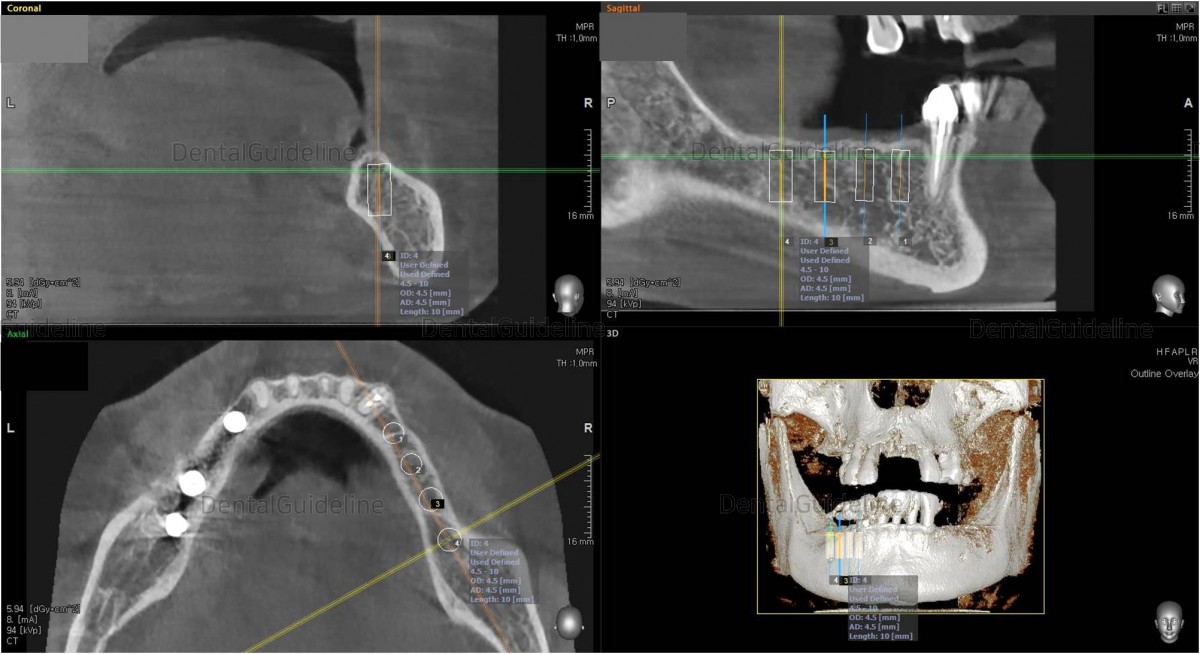

Simple

simulation of implant placement on the CBCT scan image![]()

CBCT

scan. Arum NB-1 Ø4.0/L10

(30Ncm) at the 1st premolar zone.

![]()

CBCT scan Arum NB-1 Ø4.5./ L10

(20Ncm) at

the 1st molar zone.